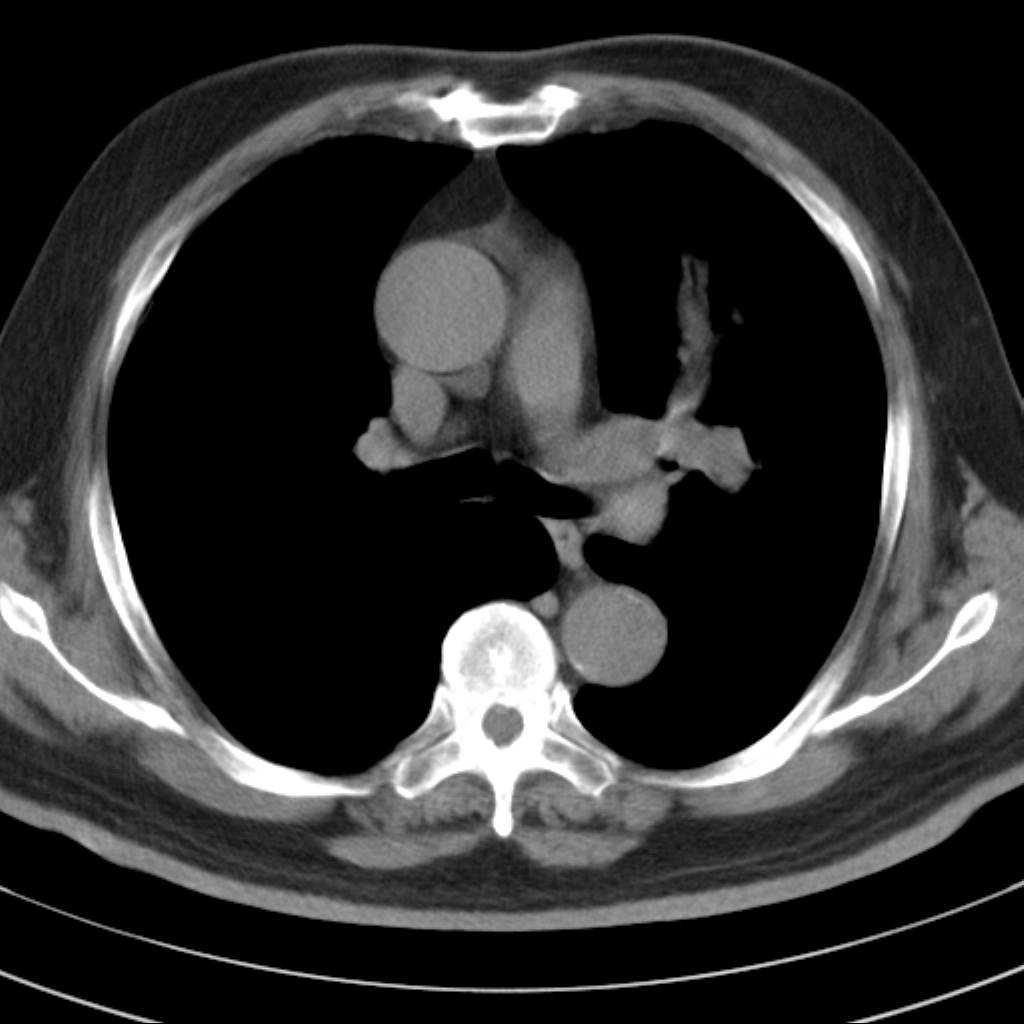

左肺动静脉畸形,肺动静脉畸形(pavms)是肺血管发育异常,是肺动脉与肺静脉直接相通形成短路,通常包括一条供血动脉及一条或数条引流静脉,以及他们之间的异常血管团。约70%的患者伴发遗传性出血性毛细血管扩张症。 影像检查的目的在于确定病灶位置、大小、形态、数目。x线可表现为:1.结节型(直径小于3cm)2.团块型(直径大于3cm)3.弥漫型(肺内散在逗点状影),以团块状居多。 ct扫描可见单发或多发肺内结节,有的有蜿蜒迂曲的团块影,边缘光滑、锐利,增强ct扫描可见增粗、扭曲的血管影和/或类圆形的增粗的血管断面,甚至供血动脉及引流静脉。

平扫似avm,建议增强扫描。

病人已经去做mr了  等待结果中  有消息 我会进一步将结果发在网上